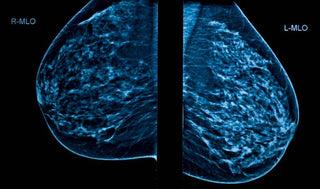

There are four categories of breast density ranging from almost entirely fatty to extremely dense. Breast density is not related to breast size or firmness but can be determined only by a mammogram.

Dense breast tissue can make it harder for radiologists to find breast cancer on a mammogram. Fatty tissue shows up as black on mammograms allowing tumors, which are white, to be seen more easily. Dense breast tissue shows up white on mammograms, making cancer harder to see on a mammogram.